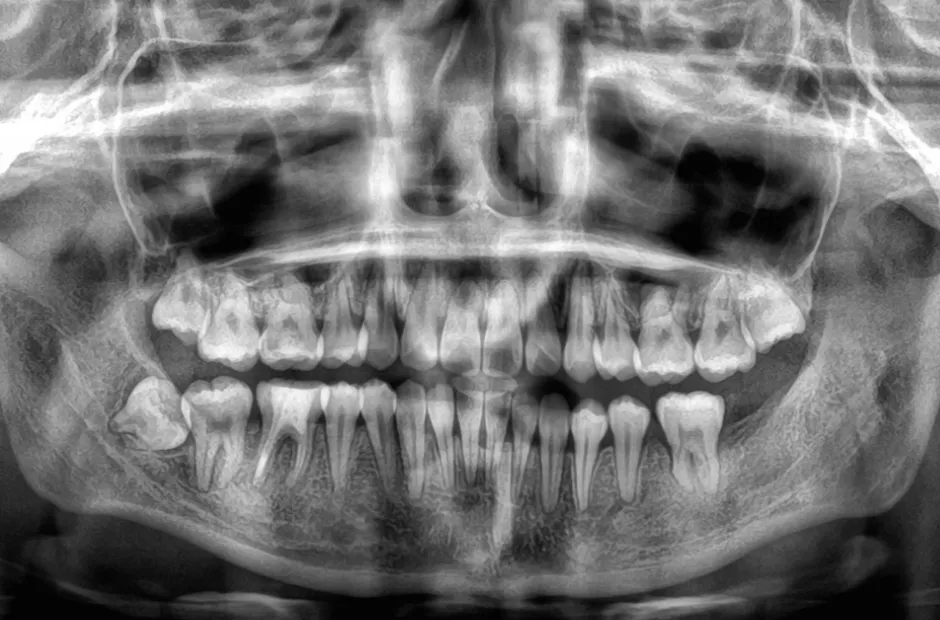

過剰歯

| 診断名・主訴 | でこぼこ |

|---|---|

| 年齢・性別 | 22歳・女性 |

| 治療期間・回数 | 1年6か月 |

| 治療に用いた主な装置 | リンガルブラケット |

| 抜歯部位 | 過剰歯 |

| 治療費 | 100万円(税抜) |

| リスク・副作用 | 装置による違和感・疼痛・歯肉退縮・歯根吸収・虫歯のリスクなど |